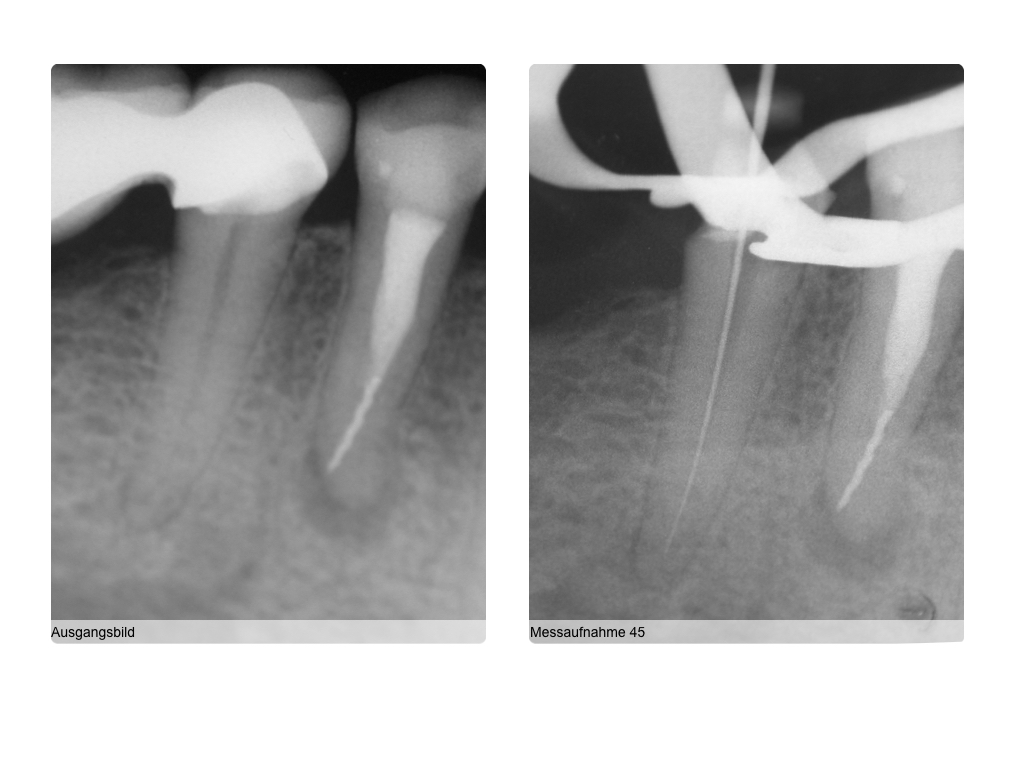

ws1442061016-001 Veröffentlicht 5. Oktober 2016 am 1024 × 768 in Zufallsrecall nach mehr als 10 Jahren